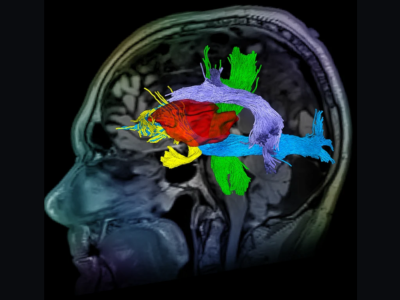

No 1 | Planifier la résection d’une tumeur cérébrale à l’aide des circuits cérébraux